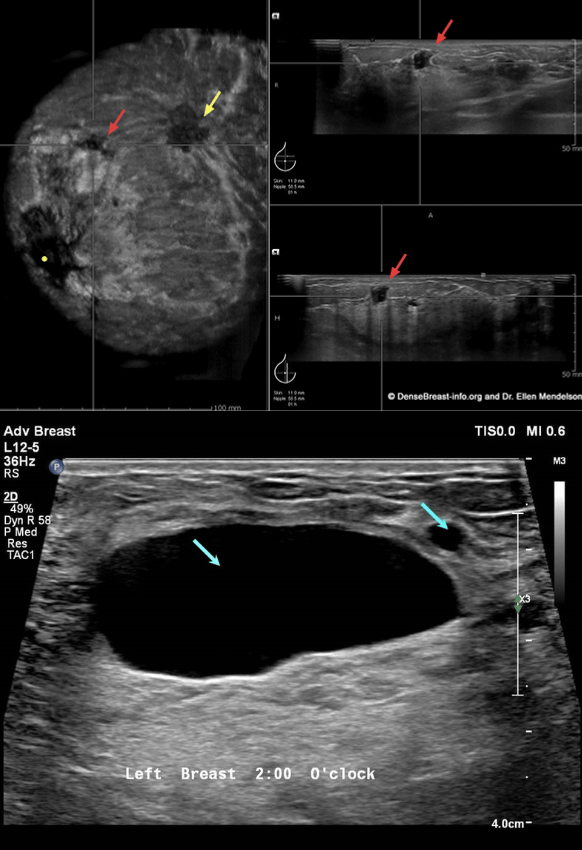

Hand-Held Ultrasound (HHUS) devices use sound waves to capture real-time images of the breast, particularly useful for identifying lumps or abnormalities.

Pros:

Radiation-free and non-invasive.

Effective for dense breast tissue.

Comfortable. Since there’s no compression involved, it’s a pain-free option.

Provides a real-time picture of the breast.

Cons:

Operator-dependent. Accuracy of the results can depend on the skill of the technician performing the ultrasound.

Takes more time than other screening methods.

Can only detect calcifications if they are large.